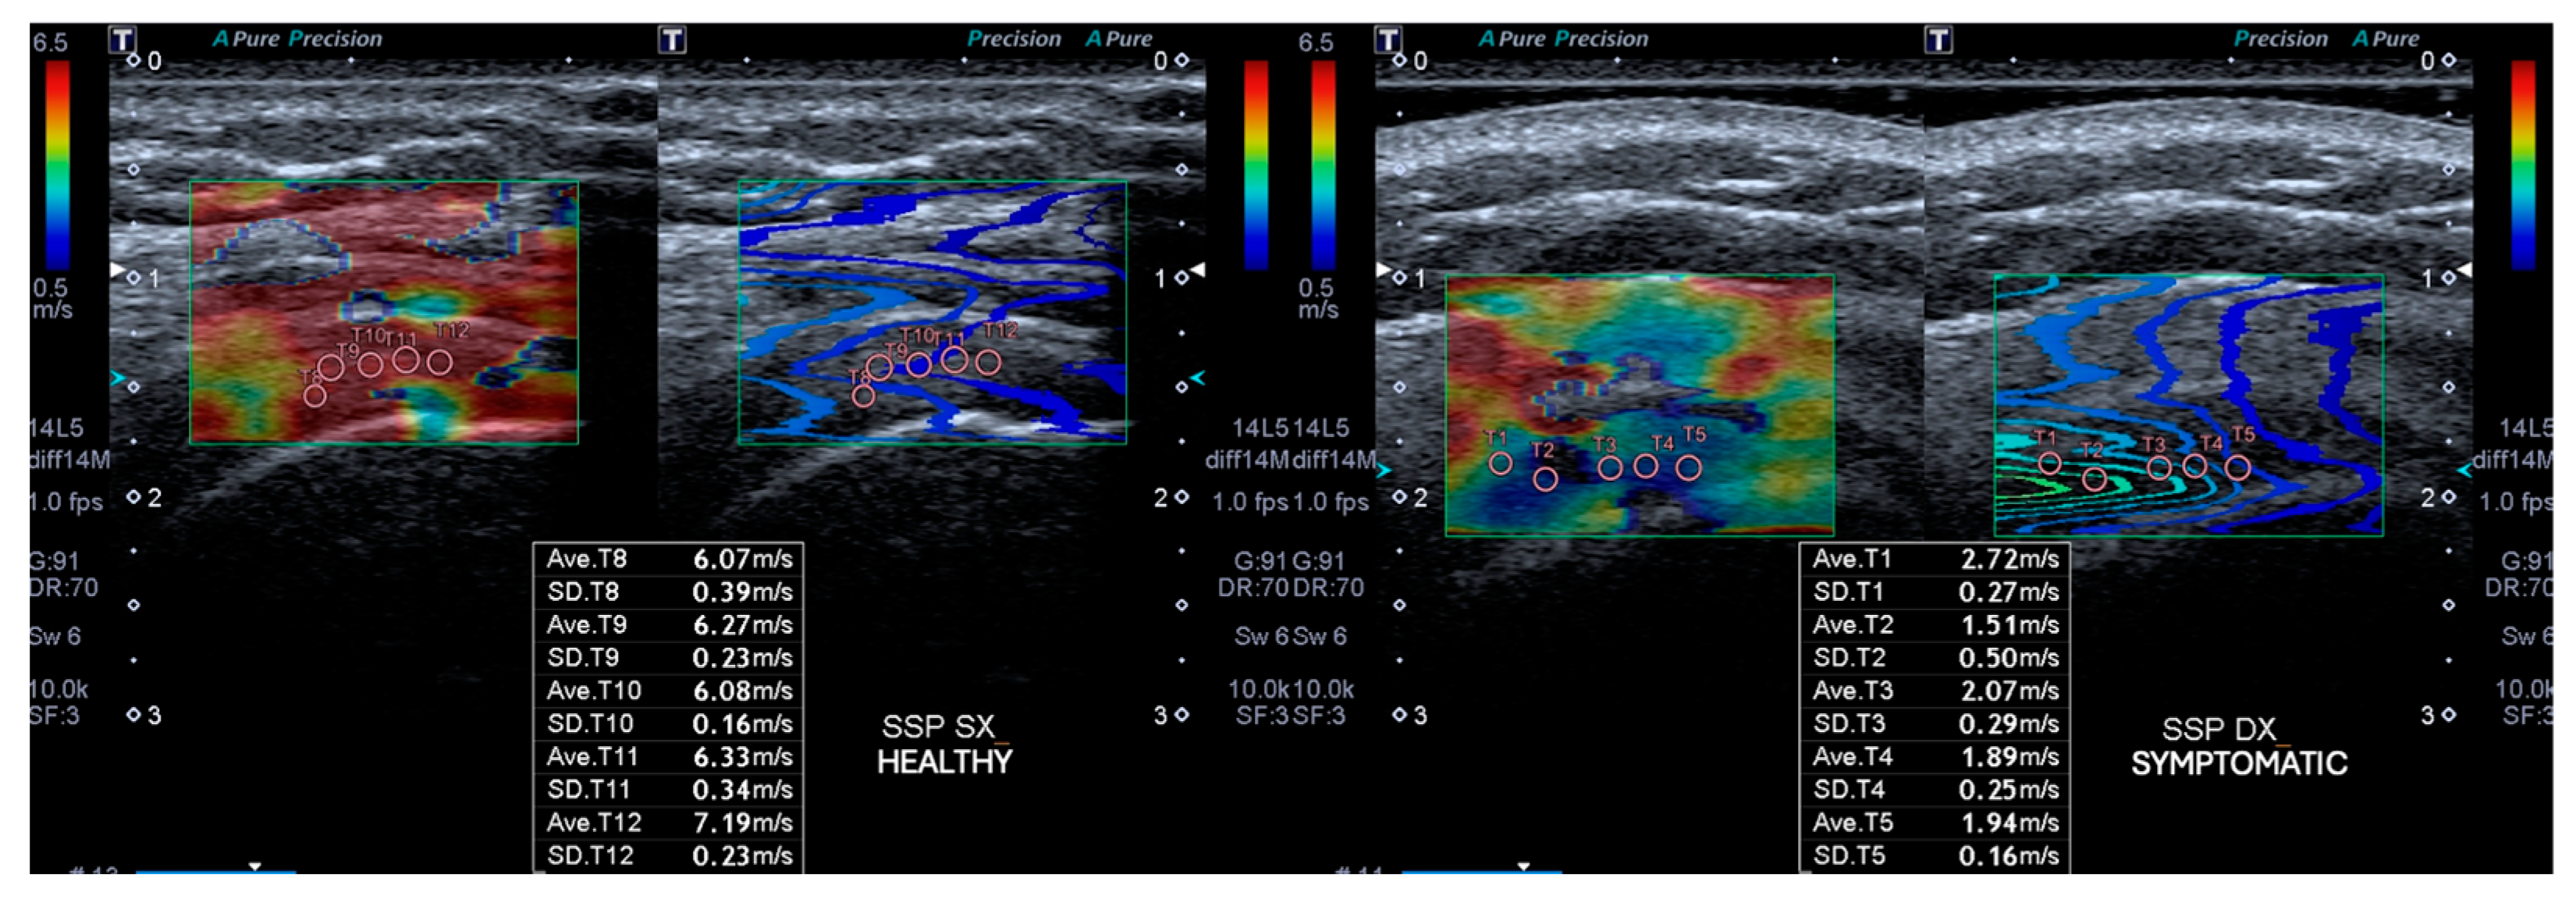

2.2.1. Outcomes Ultrasound Evaluation

2.2.2. Ultrasound Evaluation

| SWEv affected side T0 | 3 ± 0.7 |

| SWEv affected side T1 | 5.7 ± 1.8 |

| SWEv healthy side T0 | 6.9 ± 1 |

| Symptomatic SSP T0 | Symptomatic SSP T1 | 95% C.I. | Healthy SSP T1 | p-Value | |

|---|---|---|---|---|---|

| Supraspinatus Thickness | 7.5 ± 0.9 | 6.2 ± 0.9 | −0.9 to −1.6 | 4.5 ± 0.7 | <0.05 |

| SWEv (m/s) | 3.1 ± 0.7 | 5.7 ± 1.8 | 3.2 to 2.1 | 6.9 ± 1 | <0.05 |